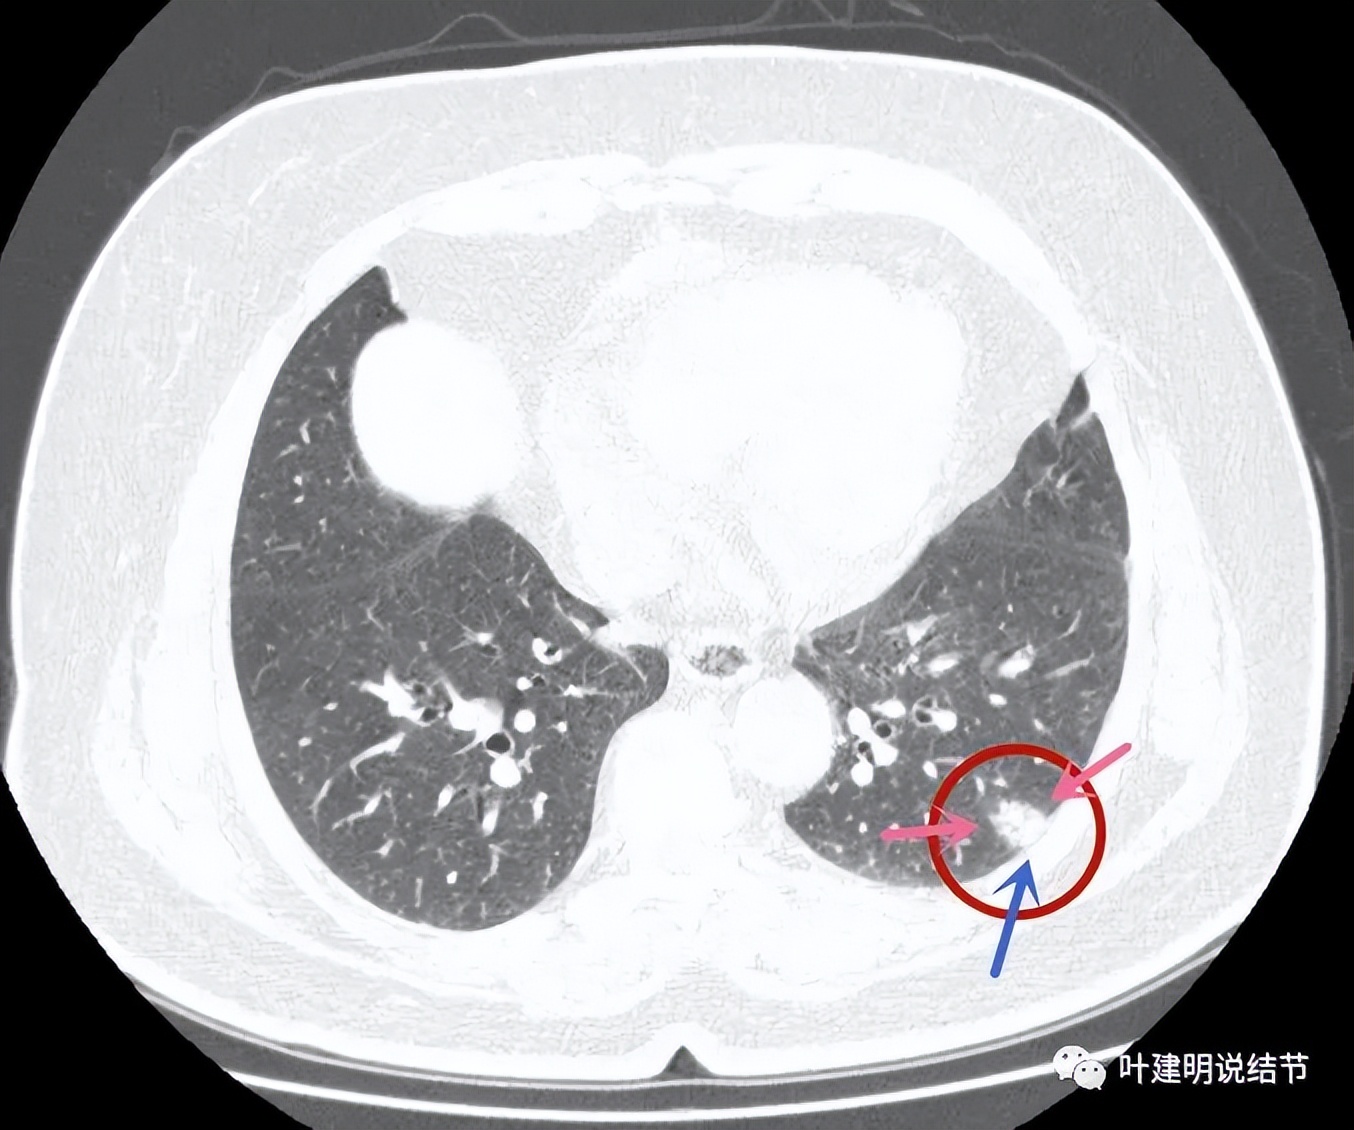

病灶4:左下叶实性结节,即主病灶,实性不是很致密的病灶,胸膜下,边界较清,邻近胸膜没有牵拉。有恶性可能性(良性的用什么疾病能解释?好像错构瘤、硬化性血管瘤、结核、肉芽肿性炎、淋巴结、急性炎症、隐球菌等常见的都靠不太上)。

病灶4:见有血管进入病灶,整体上是偏实性的,但感觉不太致密

病灶出现,磨玻璃部分密度过低,边缘有实性成分,贴着胸膜

病灶近肺门侧有斑片状磨玻璃影(绿色箭头),病灶与胸壁间贴着,但没有牵拉(蓝色箭头),大部分是实性密度(粉色箭头)。